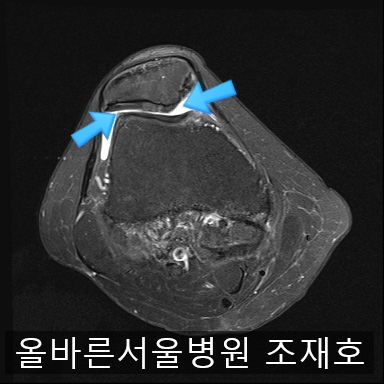

为了掌握具体情况拍了MRI。

内侧关节软骨几乎不见,软骨板也受损严重。软骨损伤部位充满关节液。

软骨板损伤严重